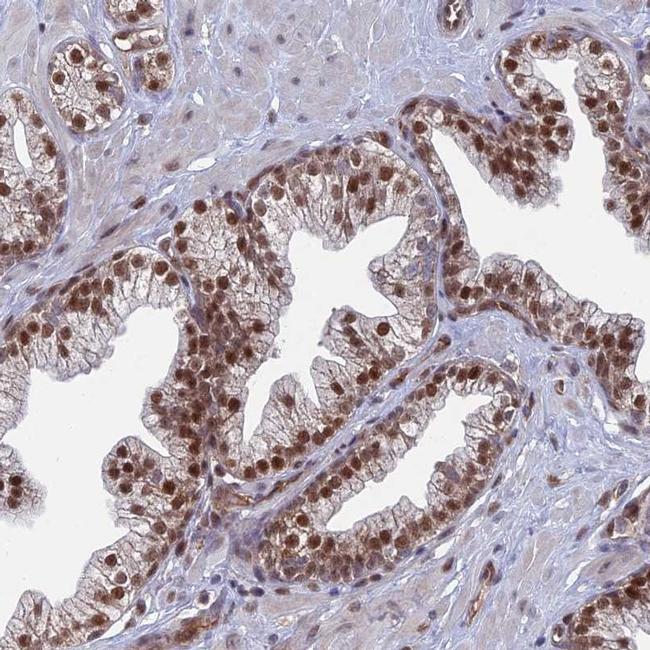

- Main image

- Experimental details

- Immunohistochemical staining of UNC5D in human prostate shows distinct nuclear positivity in glandular cells. Samples were probed using an UNC5D Polyclonal Antibody (Product # PA5-60168).